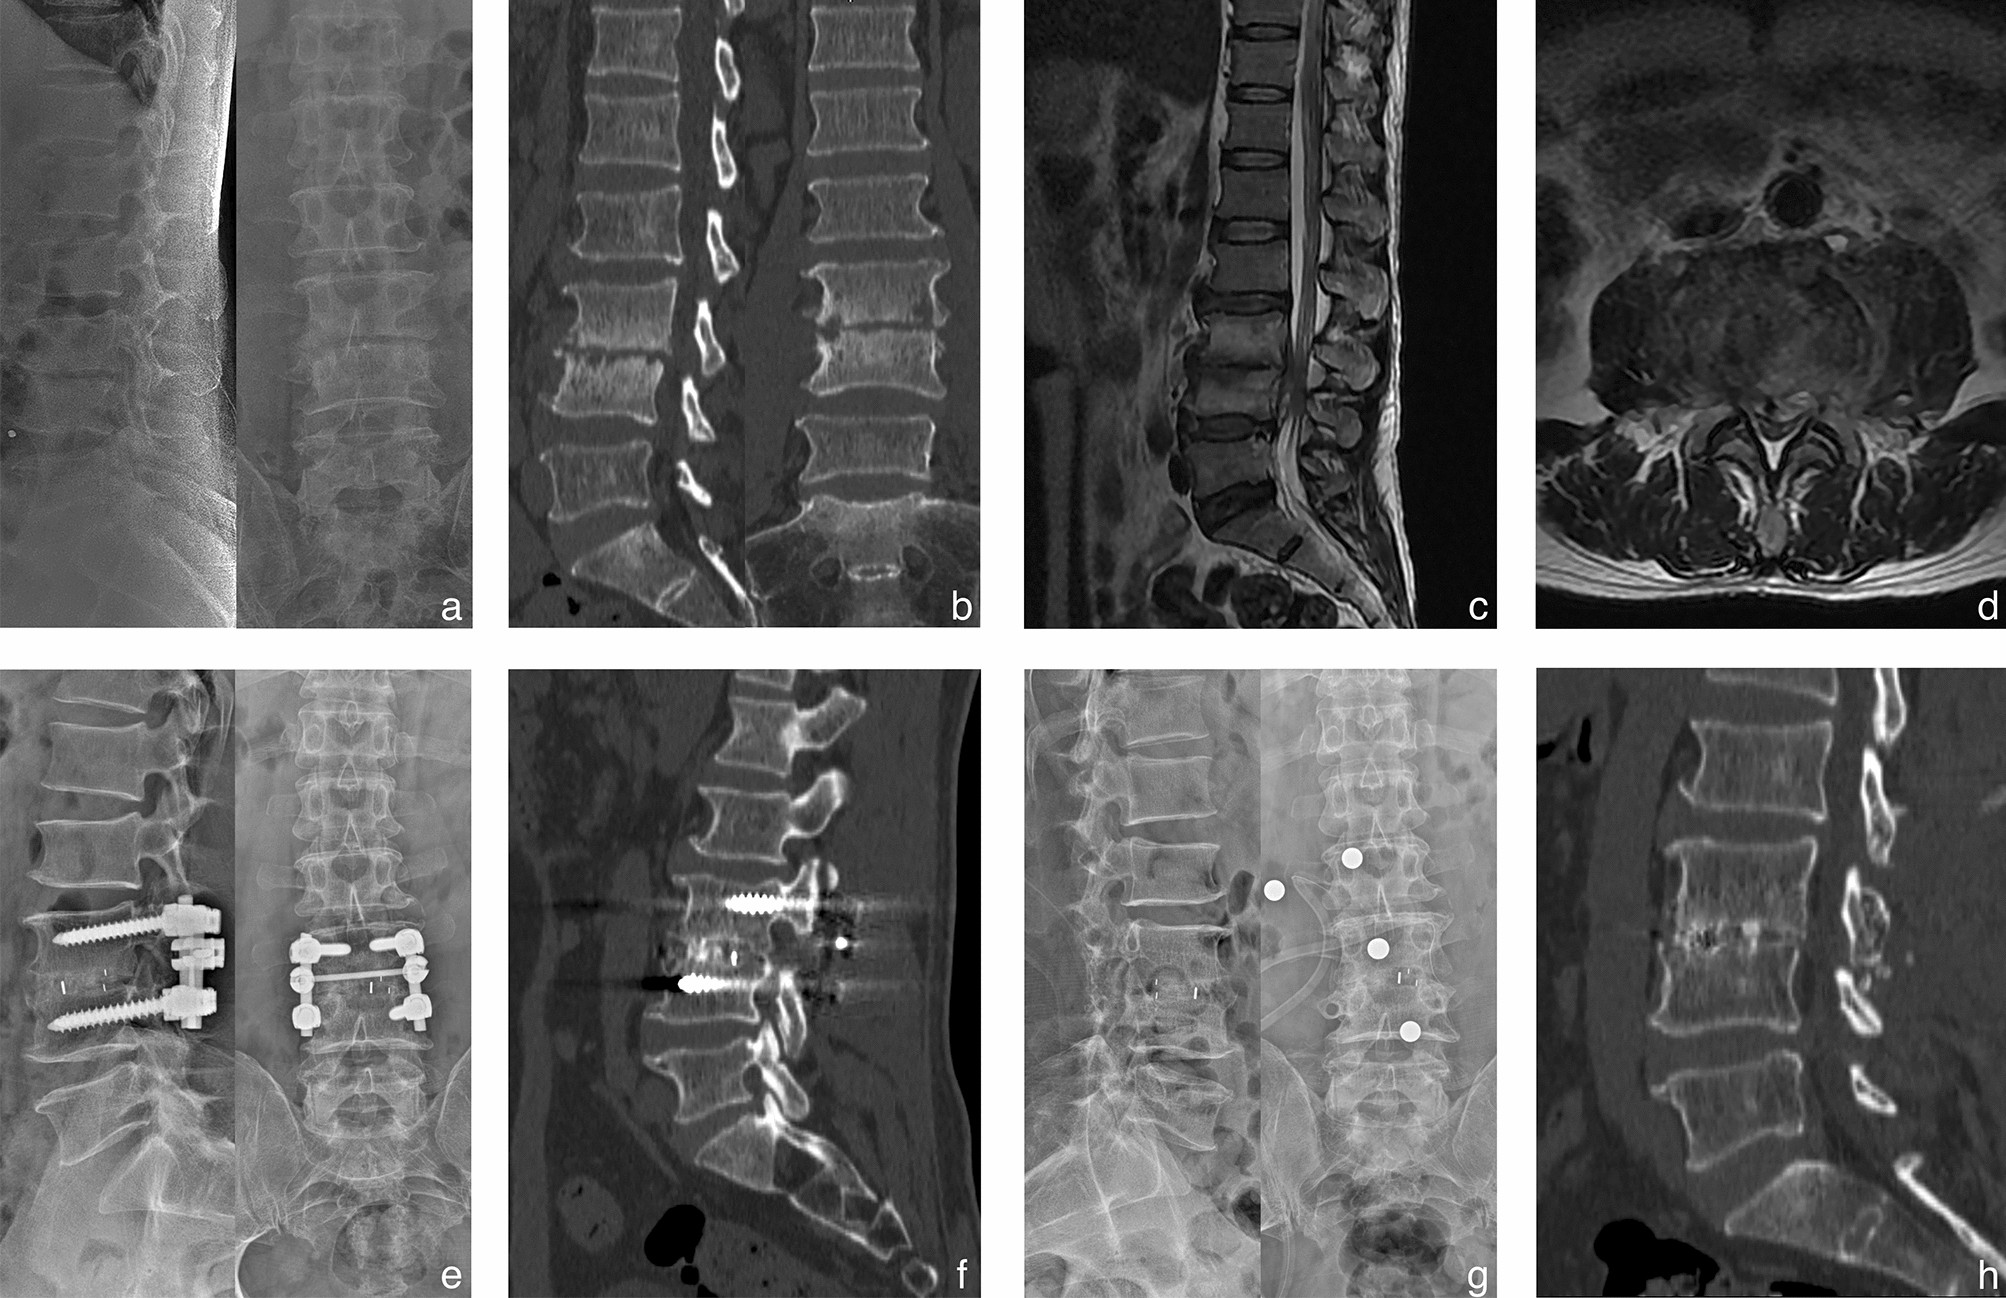

Figure 1

A 53-year-old male shepherd diagnosed with L3-4 brucella spondylitis underwent one-stage posterior interbody fusion and debridement procedure. Preoperative X-ray revealed intervertebral height loss and significant narrowing of the affected disc space. Preoperative CT and MRI scans exhibited erosions of the superior and inferior endplates, along with evidence of nerve compression. (a–d) Postoperative X-ray and CT images demonstrated satisfactory positioning of the internal fixation and cage. (e–f) The final follow-up conducted at 26 months indicated successful bone fusion following the removal of instrumentation, as evidenced by radiographic and CT examinations (g–h).